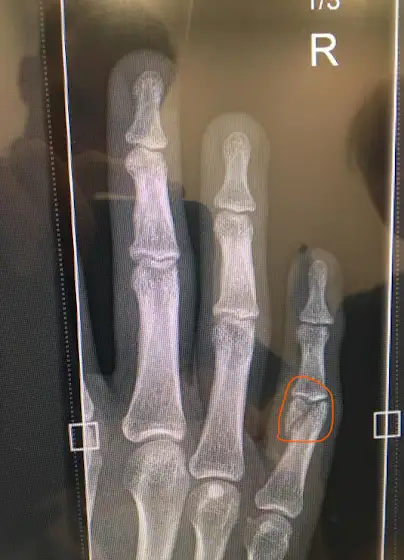

I've broken my finger and it's a bad break. I need to have an operation to put it mostly right. Long story short, you won't hear much from me for a wee while as I find it quite hard to do things such as animating with one and a bit hands.

I've broken my finger and it's a bad break.

I need to have an operation to put it mostly right.